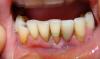

gulnaz_nuris Опубликовано 28 мая, 2011 Поделиться Опубликовано 28 мая, 2011 Здравствуйте, на нижней десне вокруг переднего зуба месяц назад образовалось воспаление - десна белого цвета, не отечна, без гноя, по снимку воспаления на корне нет. месяц назад рядом стоящий зуб расшатался и выпал, затем зубной ряд был восстановлен шинированием всех передних нижних зубов. Стоматолог осматривая зуб в течение месяца не может сказать что это за воспаление, с чем оно связано и что явилось причиной. Ссылается на возможный ожог образовавшийся в результате прикладывания на воспаленный участок десны растительных препаратов. Хотя это не так. Прикладовались примочки из заваренных трав - зверобоя или ромашки, при отказе от примочек белесость не проходит.что можете посоветовать? Зуб не болит, просто белая десна вокруг зуба. Ссылка на комментарий

gulnaz_nuris Опубликовано 29 мая, 2011 Автор Поделиться Опубликовано 29 мая, 2011 зуб стоит рядом с выпавшим. это соседний зуб отмеченный маркером на снимке и на фото. десна воспалена вокруг реально существующего зуба. а шинированием был востановлен зубной ряд- муляжом.как вы думаете с чем может быть связано белесая десна (ободок вокруг зуба) под здоровым существующим зубом? Ссылка на комментарий